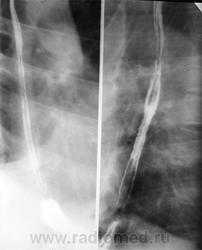

в — нижняя треть пищевода; г — сагиттальная реконструкция Картина нормального пищевода при рентгенологическом исследовании при тугом наполнении и двойном контрастировании:

а — в норме пищевод при тугом наполнении имеет диаметр около 2 см, четкие и ровные контуры;

б — после прохождения контрастной массы выявляются продольные непрерывные складки слизистой оболочки (до 4)